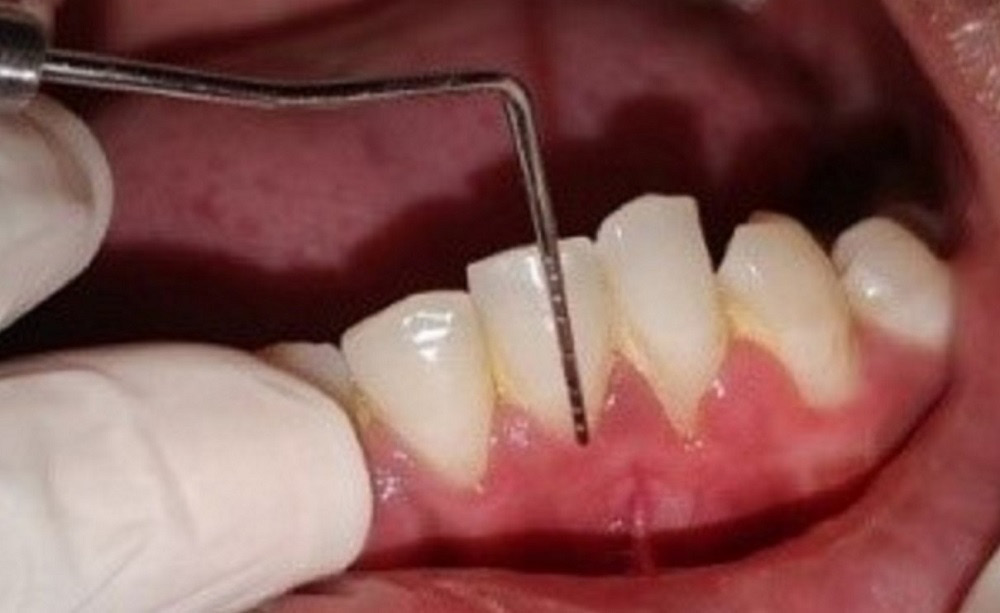

Estimation of the clinical parameters

The recession depth, GT, PD, CAL, and KTW were assessed using a Williams probe at baseline (D0), and 3 months (D3) and 6 months (D6) post-surgery, whereas PRC was assessed at 3 months (D3) and 6 months (D6) post-surgery. The VAS score and WHI were estimated 1 week after surgery.

Patients with Miller’s class I and II recession defects on the anterior teeth, with the probing depth (PD) >3 mm, the clinical attachment loss (CAL) >5 mm and the keratinized tissue width (KTW) >2 mm, were included in the study. Pregnant and lactating women, smokers, systemically compromised patients, subjects who had undergone the periodontal therapy in the last 6 months, and those who were on antibiotics 3 months prior to commencing the study (confirmed while recording the case history) were excluded from the study.